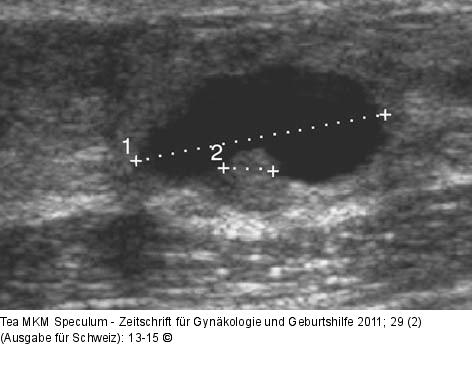

Abbildung 4: Komplexe Mammazyste Komplexe Mammazysten mit intrazystischer Raumforderung. |

Komplexe Mammazysten mit intrazystischer Raumforderung. |